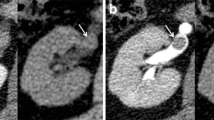

While the usual aim of excretory phase imaging in CT urography is to opacify the entire renal collecting systems with contrast, this can pose challenges for vNCT generation. Iodine subtraction became less accurate when urine densities exceeded 740 HU [29].

Oral hydration improved sensitivity of urinary calculi on vNCT by diluting the concentration of iodine excreted by the kidneys into the urinary tract by inducing mild diuresis [9]. Weatherspoon et al [10] compared oral hydration and IV hydration for CT urography and concluded there was no significant difference in the ability to dilute iodine concentration in the ureters. Oral hydration was therefore identified as the superior choice as it was more cost effective and required less resources.

Silverman et al [9] hypothesised that IV furosemide increased the concentration of iodine within urine by increasing the urine flow rate in all segments of the renal tract. This resulted in an increased opacification of the ureters. An increase in iodine concentration in the urinary collecting system resulted in a decrease in sensitivity of the vNCT for the excretory phase of the DECT urogram [26].